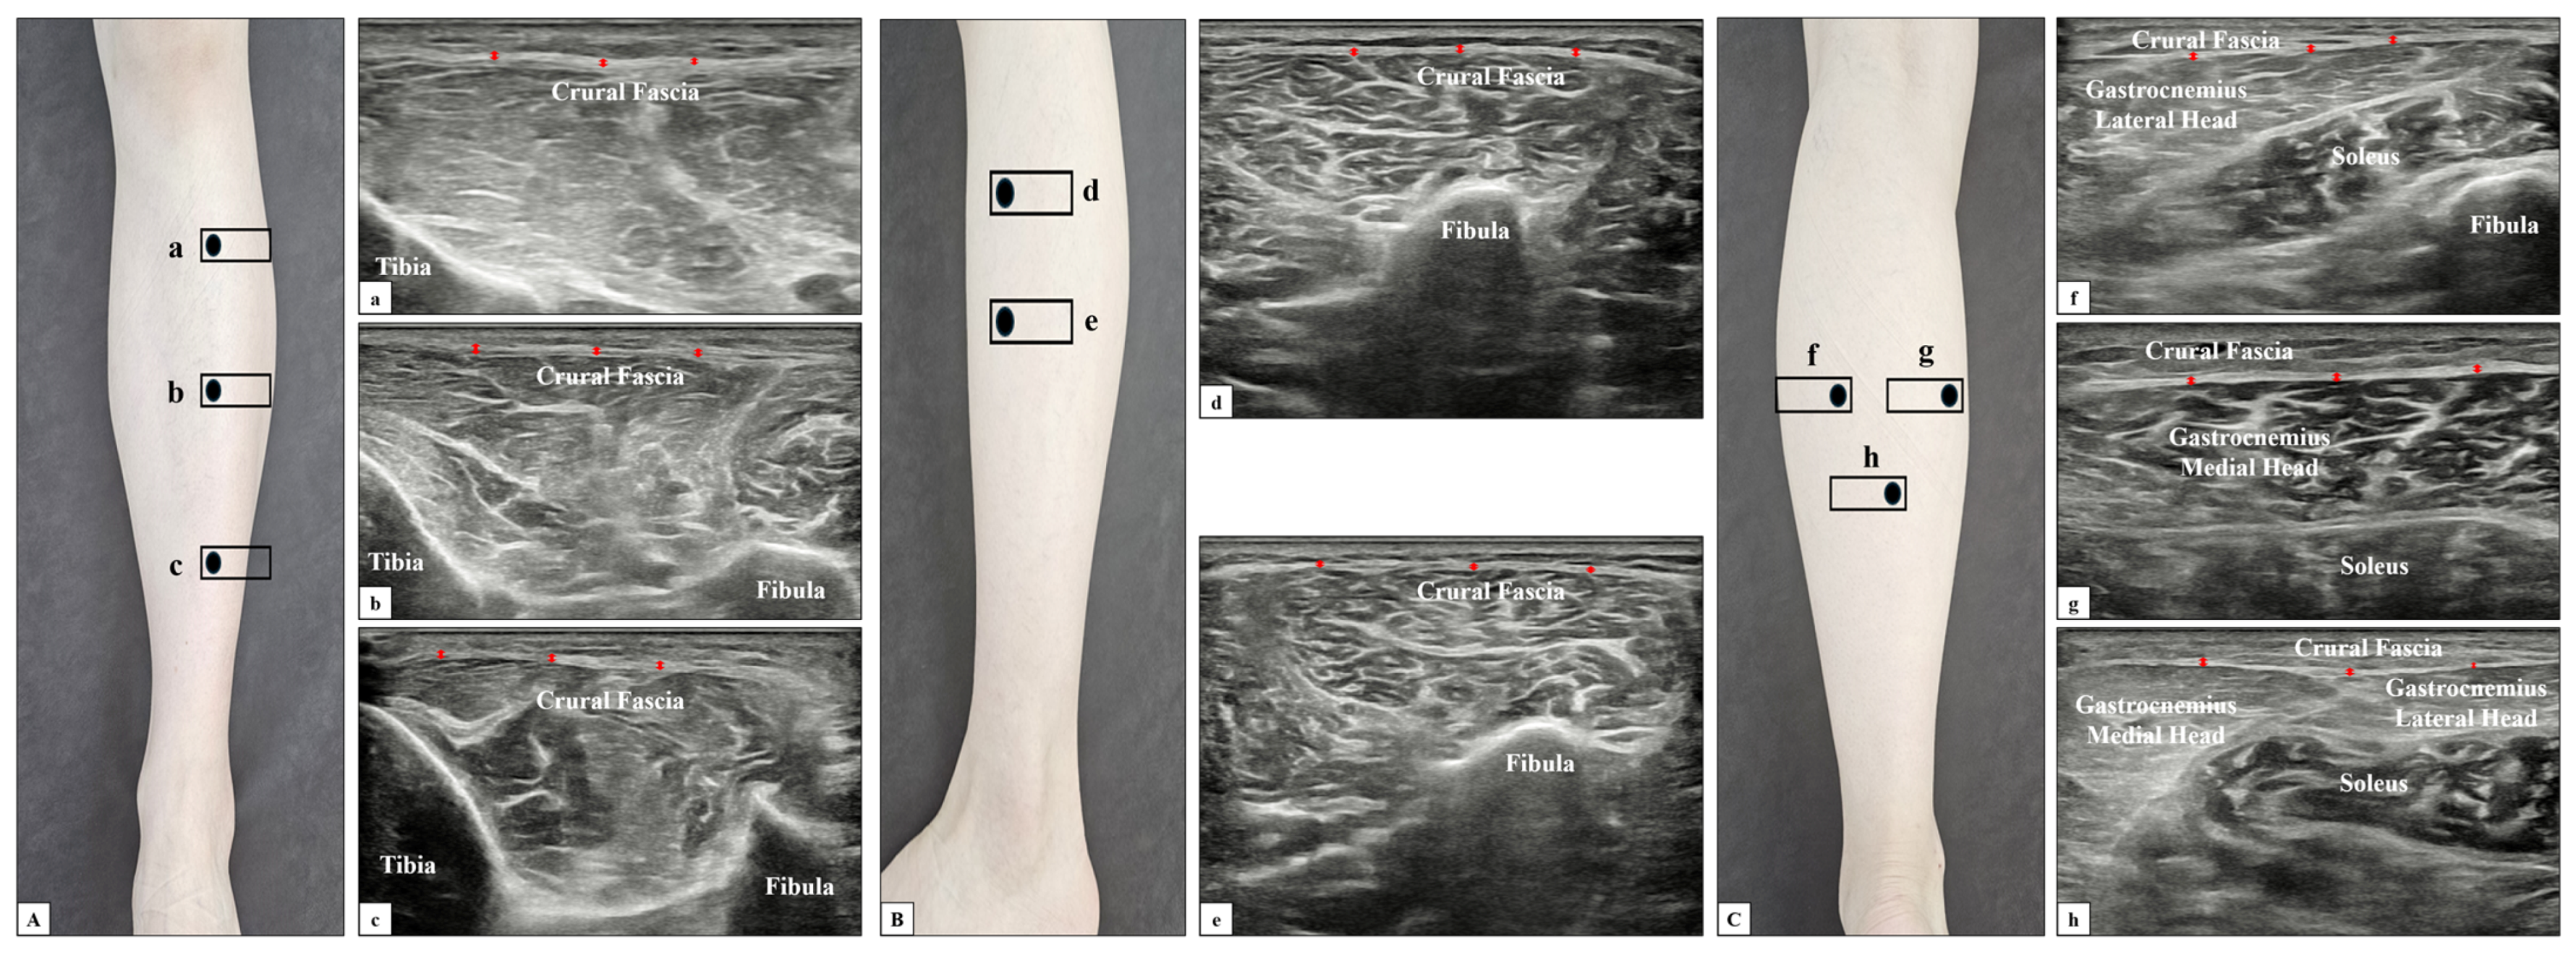

2.3.2. Fascia Thickness

| Anterior compartment of crural fascia | 0.96 ± 0.14 | 0.72 ± 0.08 | <0.001 |

| Lateral compartment of crural fascia | 1.01 ± 0.14 | 0.75 ± 0.14 | <0.001 |

| Posterior compartment of crural fascia 1 | 0.92 ± 0.22 | 0.68 ± 0.11 | <0.001 |

| Posterior compartment of crural fascia 2 | 0.96 ± 0.21 | 0.72 ± 0.16 | <0.001 |

| Posterior compartment of crural fascia 3 | 1.02 ± 0.30 | 0.77 ± 0.16 | <0.001 |

| Tibialis anterior epimysial fascia | 0.46 ± 0.07 | 0.34 ± 0.03 | <0.001 |